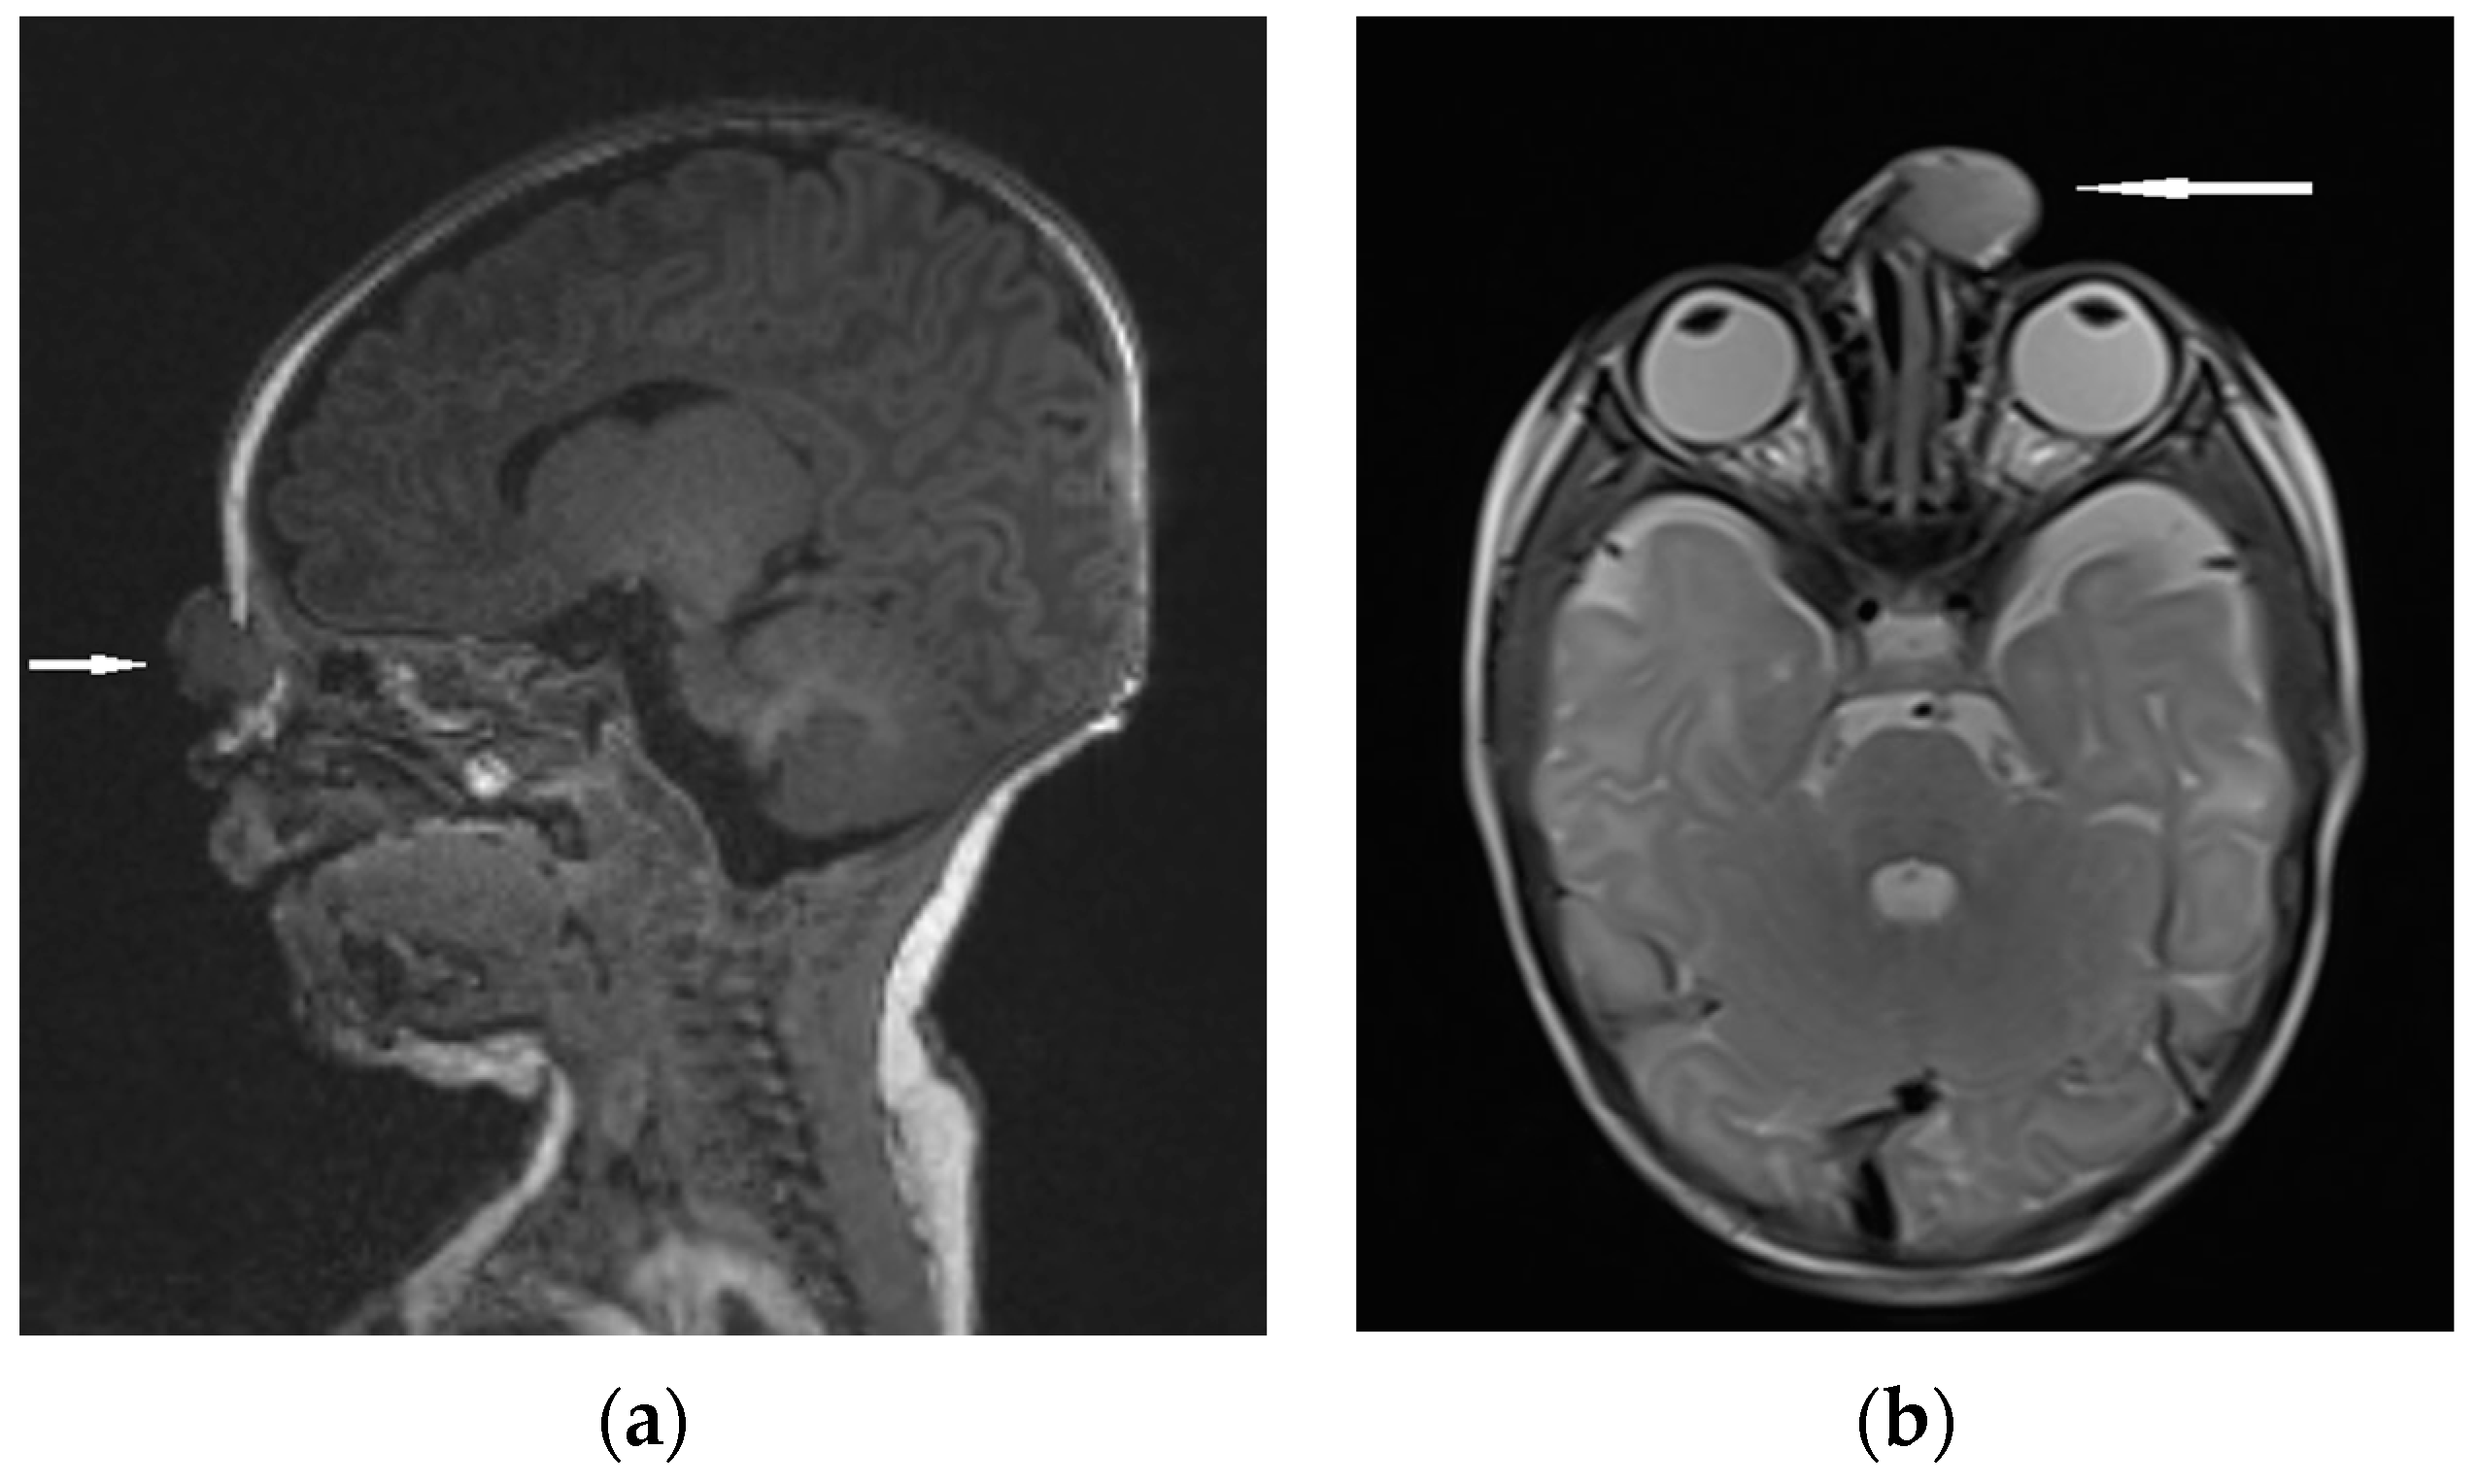

| MRI | Variable signal intensity depending on the protein content; fat-suppressed T1-weighted images—differentiation between skull base defects and enhancing non-ossified cartilage of anterior cranial fossa; DWI—typically high-signal-intensity lesion with corresponding low signal intensity on ADC maps | Discontinuity with the brain parenchyma; variable visualization of a fibrous stalk connection to CNS; well-circumscribed, rounded, or polypoid mass—isointense or rarely hypointense to gray matter on T1-weighted imaging; neural tissue—more hyperintense on T2-weighted images to normal brain parenchyma in most cases; dysplastic tissue usually corresponds with no enhancement or moderate enhancement; noticeable enhancement at the lesion periphery | Herniation of intracranial tissue and its continuity with the brain | |